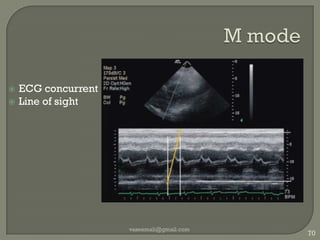

M modeBrightness α intensity of reflected signalPosition of moving reflectorsRapid motion :  cardiac valvesvaseemali@gmail.com68Essentials of medical ultrasound: a practical introduction to the principles By Michael H. Repacholi, Dierdre A. Benwell

M modeECG concurrentLine of sightvaseemali@gmail.com70